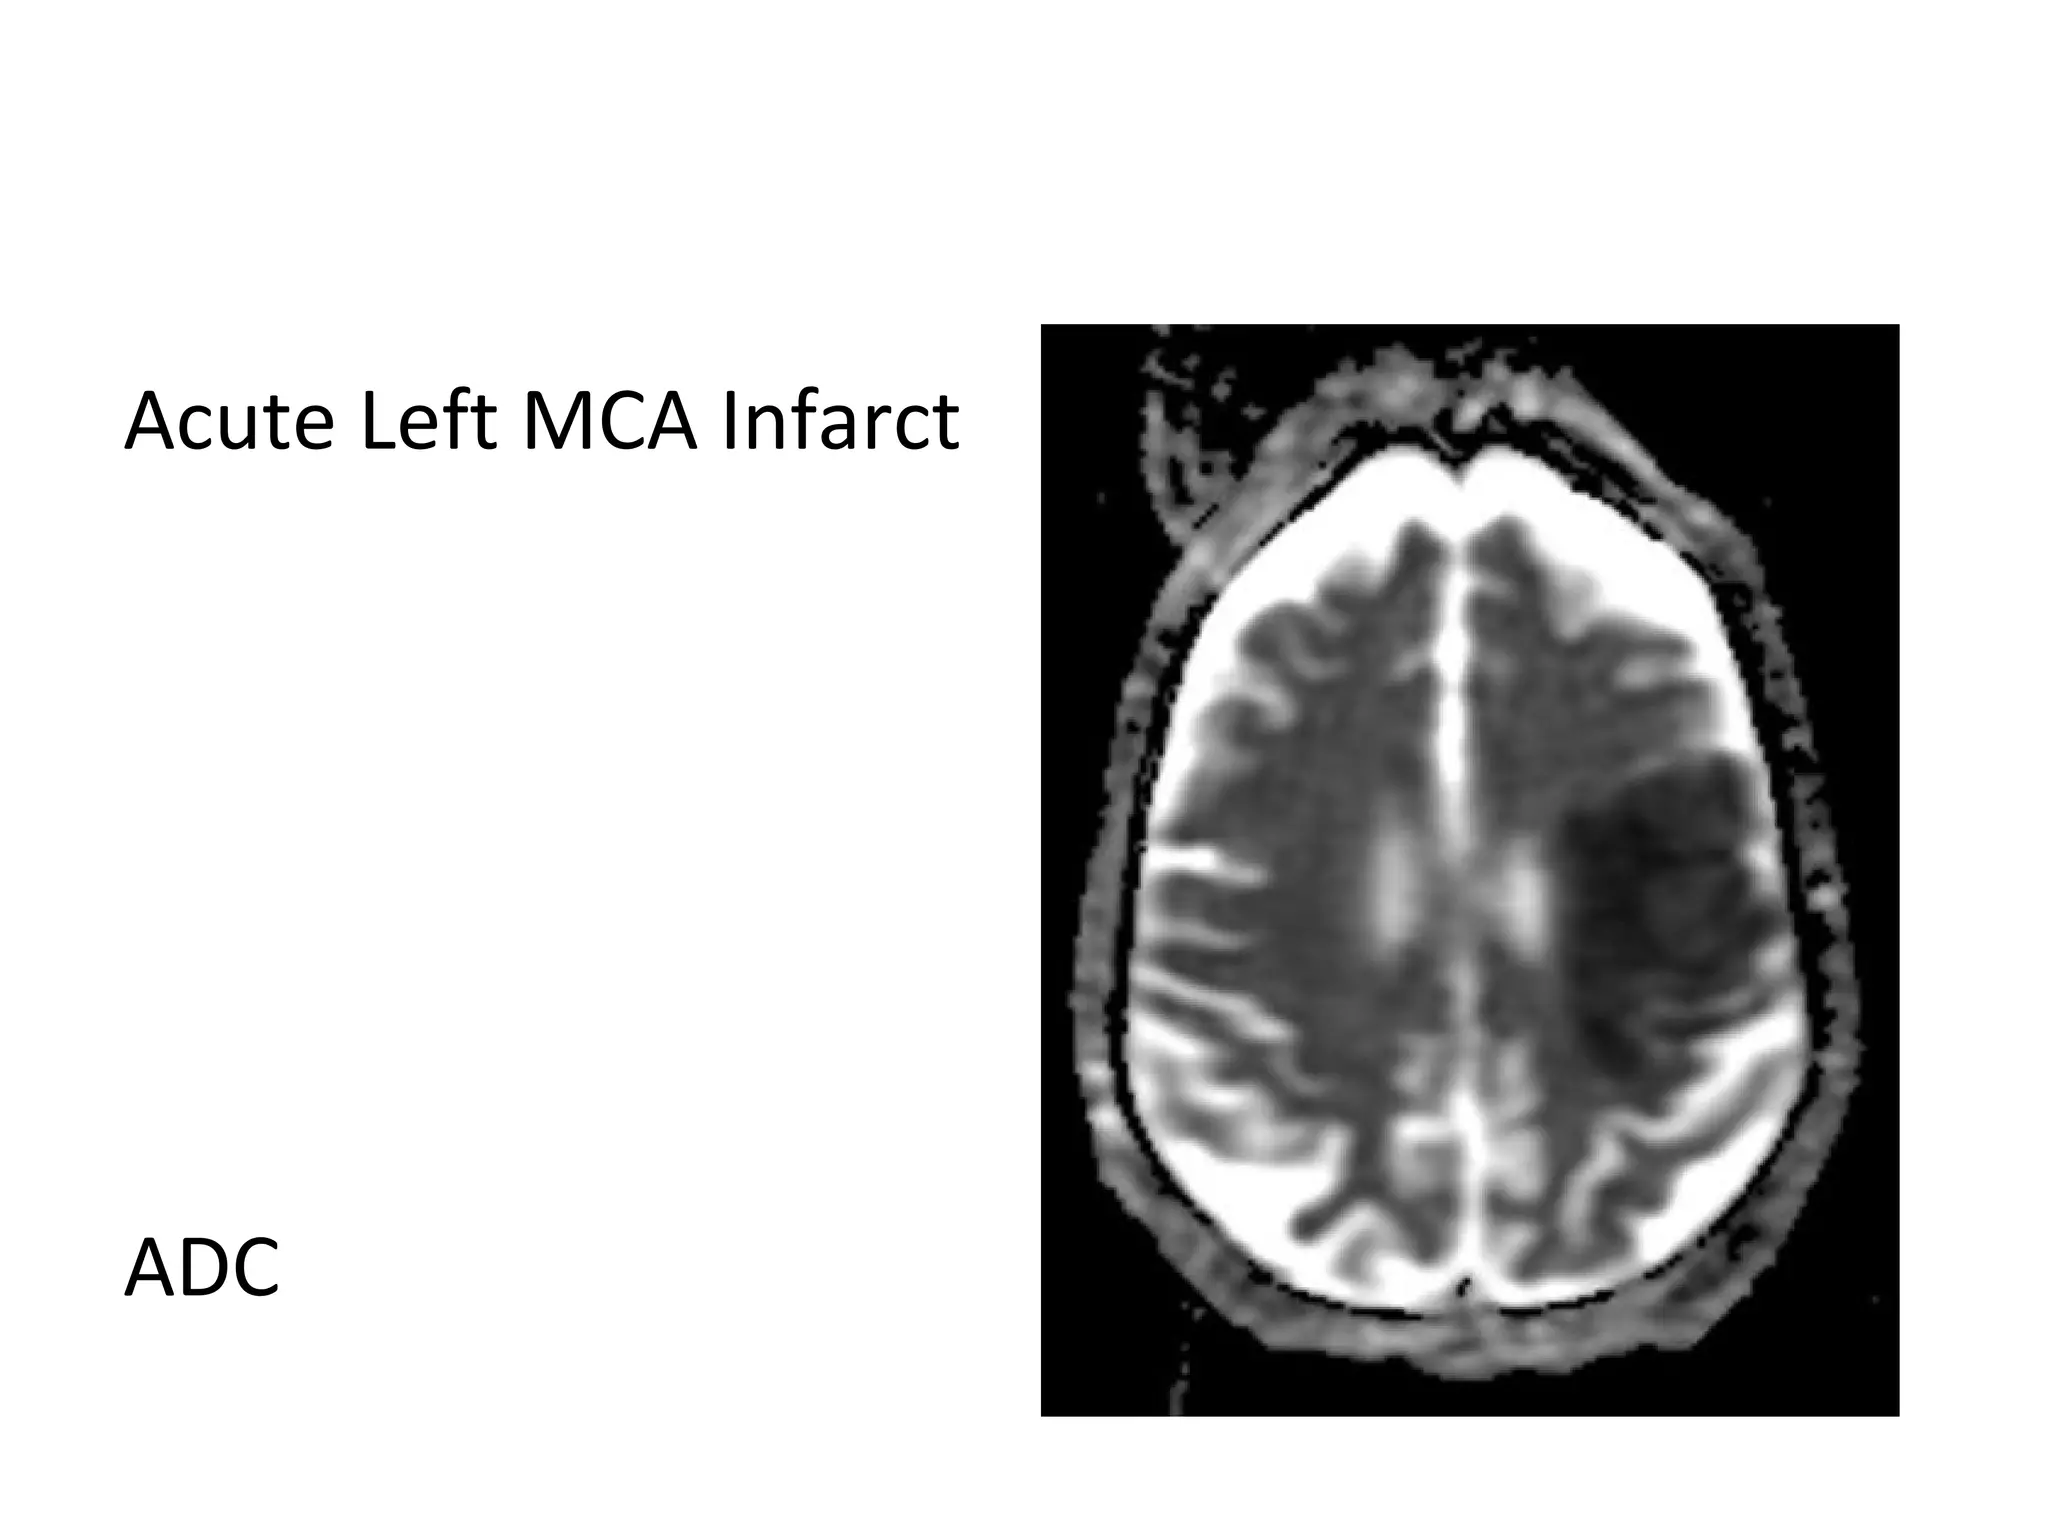

Acute Left MCA Infarct

ADC